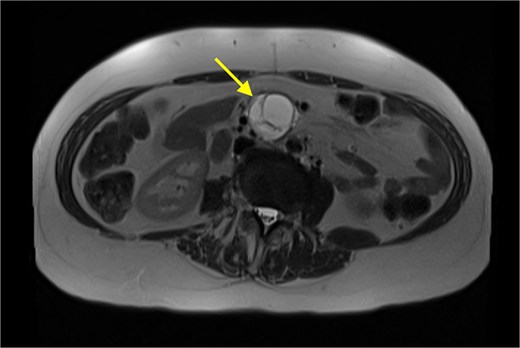

The patient’s symptoms remained stable, and she was discharged with a plan for further imaging. A fludeoxyglucose (FDG) PET scan revealed a lesion within the central mesentery with minimal FDG activity, similar to blood pooling (Fig. 2). There was a small region of mild FDG uptake at the posterior margin of the lesion, possibly representing a mural nodule. Magnetic resonance imaging (MRI) of the abdomen revealed a well-defined T2 hyperintense cystic mass with multiple thick internal septations in the small bowel mesentery measuring 31 × 33 × 34 mm. (Fig. 3) Diagnoses included centrally necrotic pathological mesenteric node, cystic/necrotic neoplasm, cystic vascular, or lymphatic abnormality or infective pathology.

An MRI (T2 HASTE) in axial view demonstrating well-defined T2 hyperintense cystic mass (arrow).